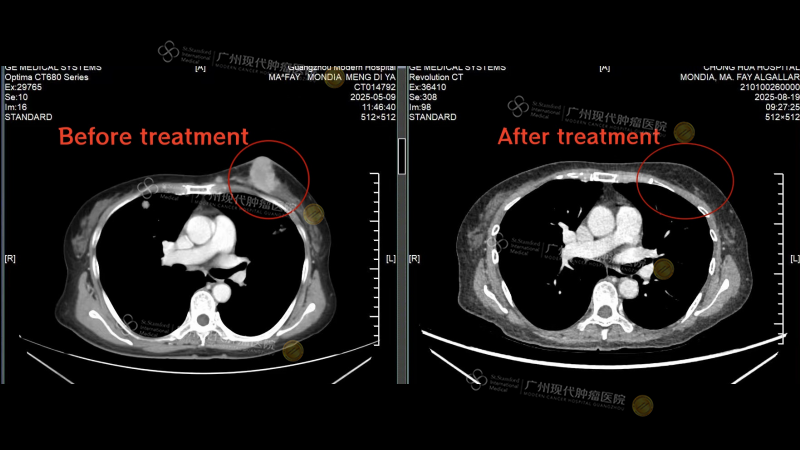

Comparison of breast tumor treatment before and after

After completing the 2nd treatment session, a follow-up CT scan at her local hospital revealed significant shrinkage of the breast tumor and the disappearance of most lung metastases. These remarkable results rekindled her hope—what she once believed was an insurmountable battle now seemed winnable at Modern Cancer Hospital Guangzhou.